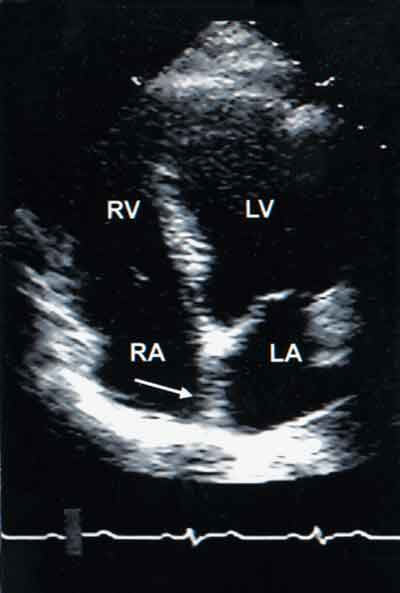

These images illustrate the transthoracic echocardiographic spectrum of IASA, with and without PFO. For comparison, a transthoracic, 2-dimensional, apical, 4-chamber view (A) shows normal interatrial septa in a 45-year-old woman who has a mass on the posterior mitral leaflet (unrelated). View B shows a typical IASA bulging into the right atrium in an asymptomatic 58-year-old man; there is no detectable PFO. View C shows a typical IASA with echo dropout (arrow) in its middle portion indicating a PFO in an asymptomatic 40-year-old woman. A color-encoded Doppler flow study confirms a small left to right shunt in the same patient (D).